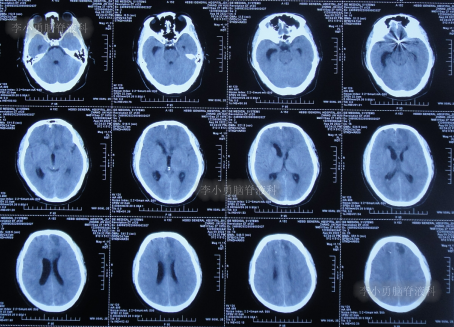

入院时头颅CT示脑室扩张,动脉瘤栓塞术后(图-11)。

图-11:入院时头颅CT

入院后次日进行了脑室外引流术(图-12)。

图-12:2022年8月25日术后头颅CT

脑室外引流术后4天即2022年8月29日,患者出现意识差,查头颅CT示左侧脑室仍扩张(图-14)。

图-14:2022年8月29日头颅CT

当天给予了左侧脑室外引流术,术后当天查头颅CT示脑室内有2根管(图-15);术后脑脊液化验出真菌。

图-15:2022年8月29日术后头颅CT